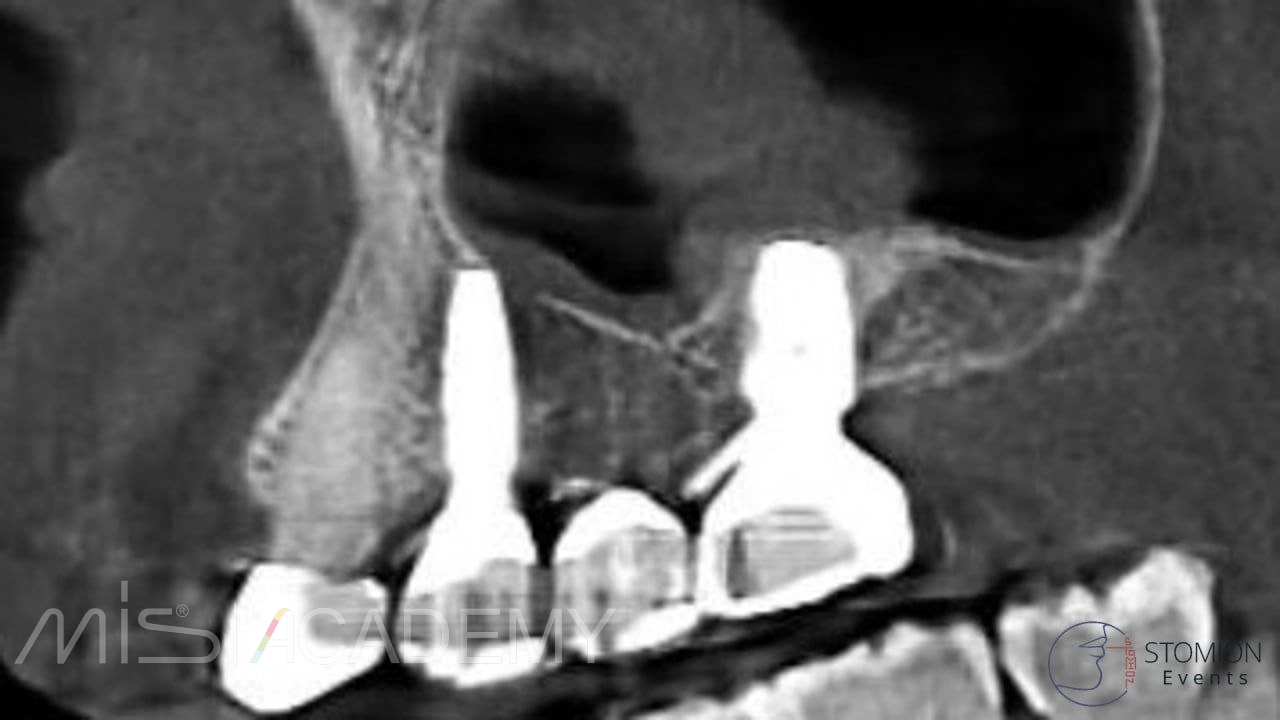

Контрольное обследование:

Через 21 месяц проведено контрольное КЛКТ-исследование. На снимках визуализируется усадка остеопластического материала над верхушкой имплантата, что связано с его аваскулярностью (отсутствием кровоснабжения).